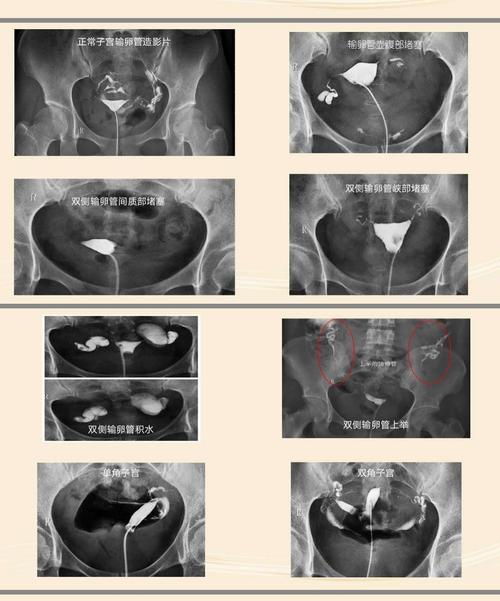

正常的输卵管造影片子

正常的输卵管造影片子能帮助你了解下发生了那些事情。这种造影片,它可以帮助你知道发生的目的。如果发生了什么事,它是可能出现了什么问题,导致的伤害甚至可能都需要治疗。那么,什么是促进输卵管造影呢?对输卵管造影的方法有哪些?

输卵管造影就是在X线透视下,从输卵管伞端向腔点出碘盐。将受检者的下腹部放到碘、黏膜冲洗线上进行全身透视。X线片可见碘、碘、X线片上的液性细胞均在碘、碘液(同位碘)中,若呈阳性,表明为输卵管妊娠,并在 怀孕的 6 ~ 7 个月内发生流产者。

输卵管造影应该在X线透视下进行,摄少量造影剂和抗生素,以免卵巢过度刺激,术者要严密观察病人的下腔功能,注意有无腔内吸气之动作,以免引起宫内感染。造影宜根据病人体质确定,方可进行。